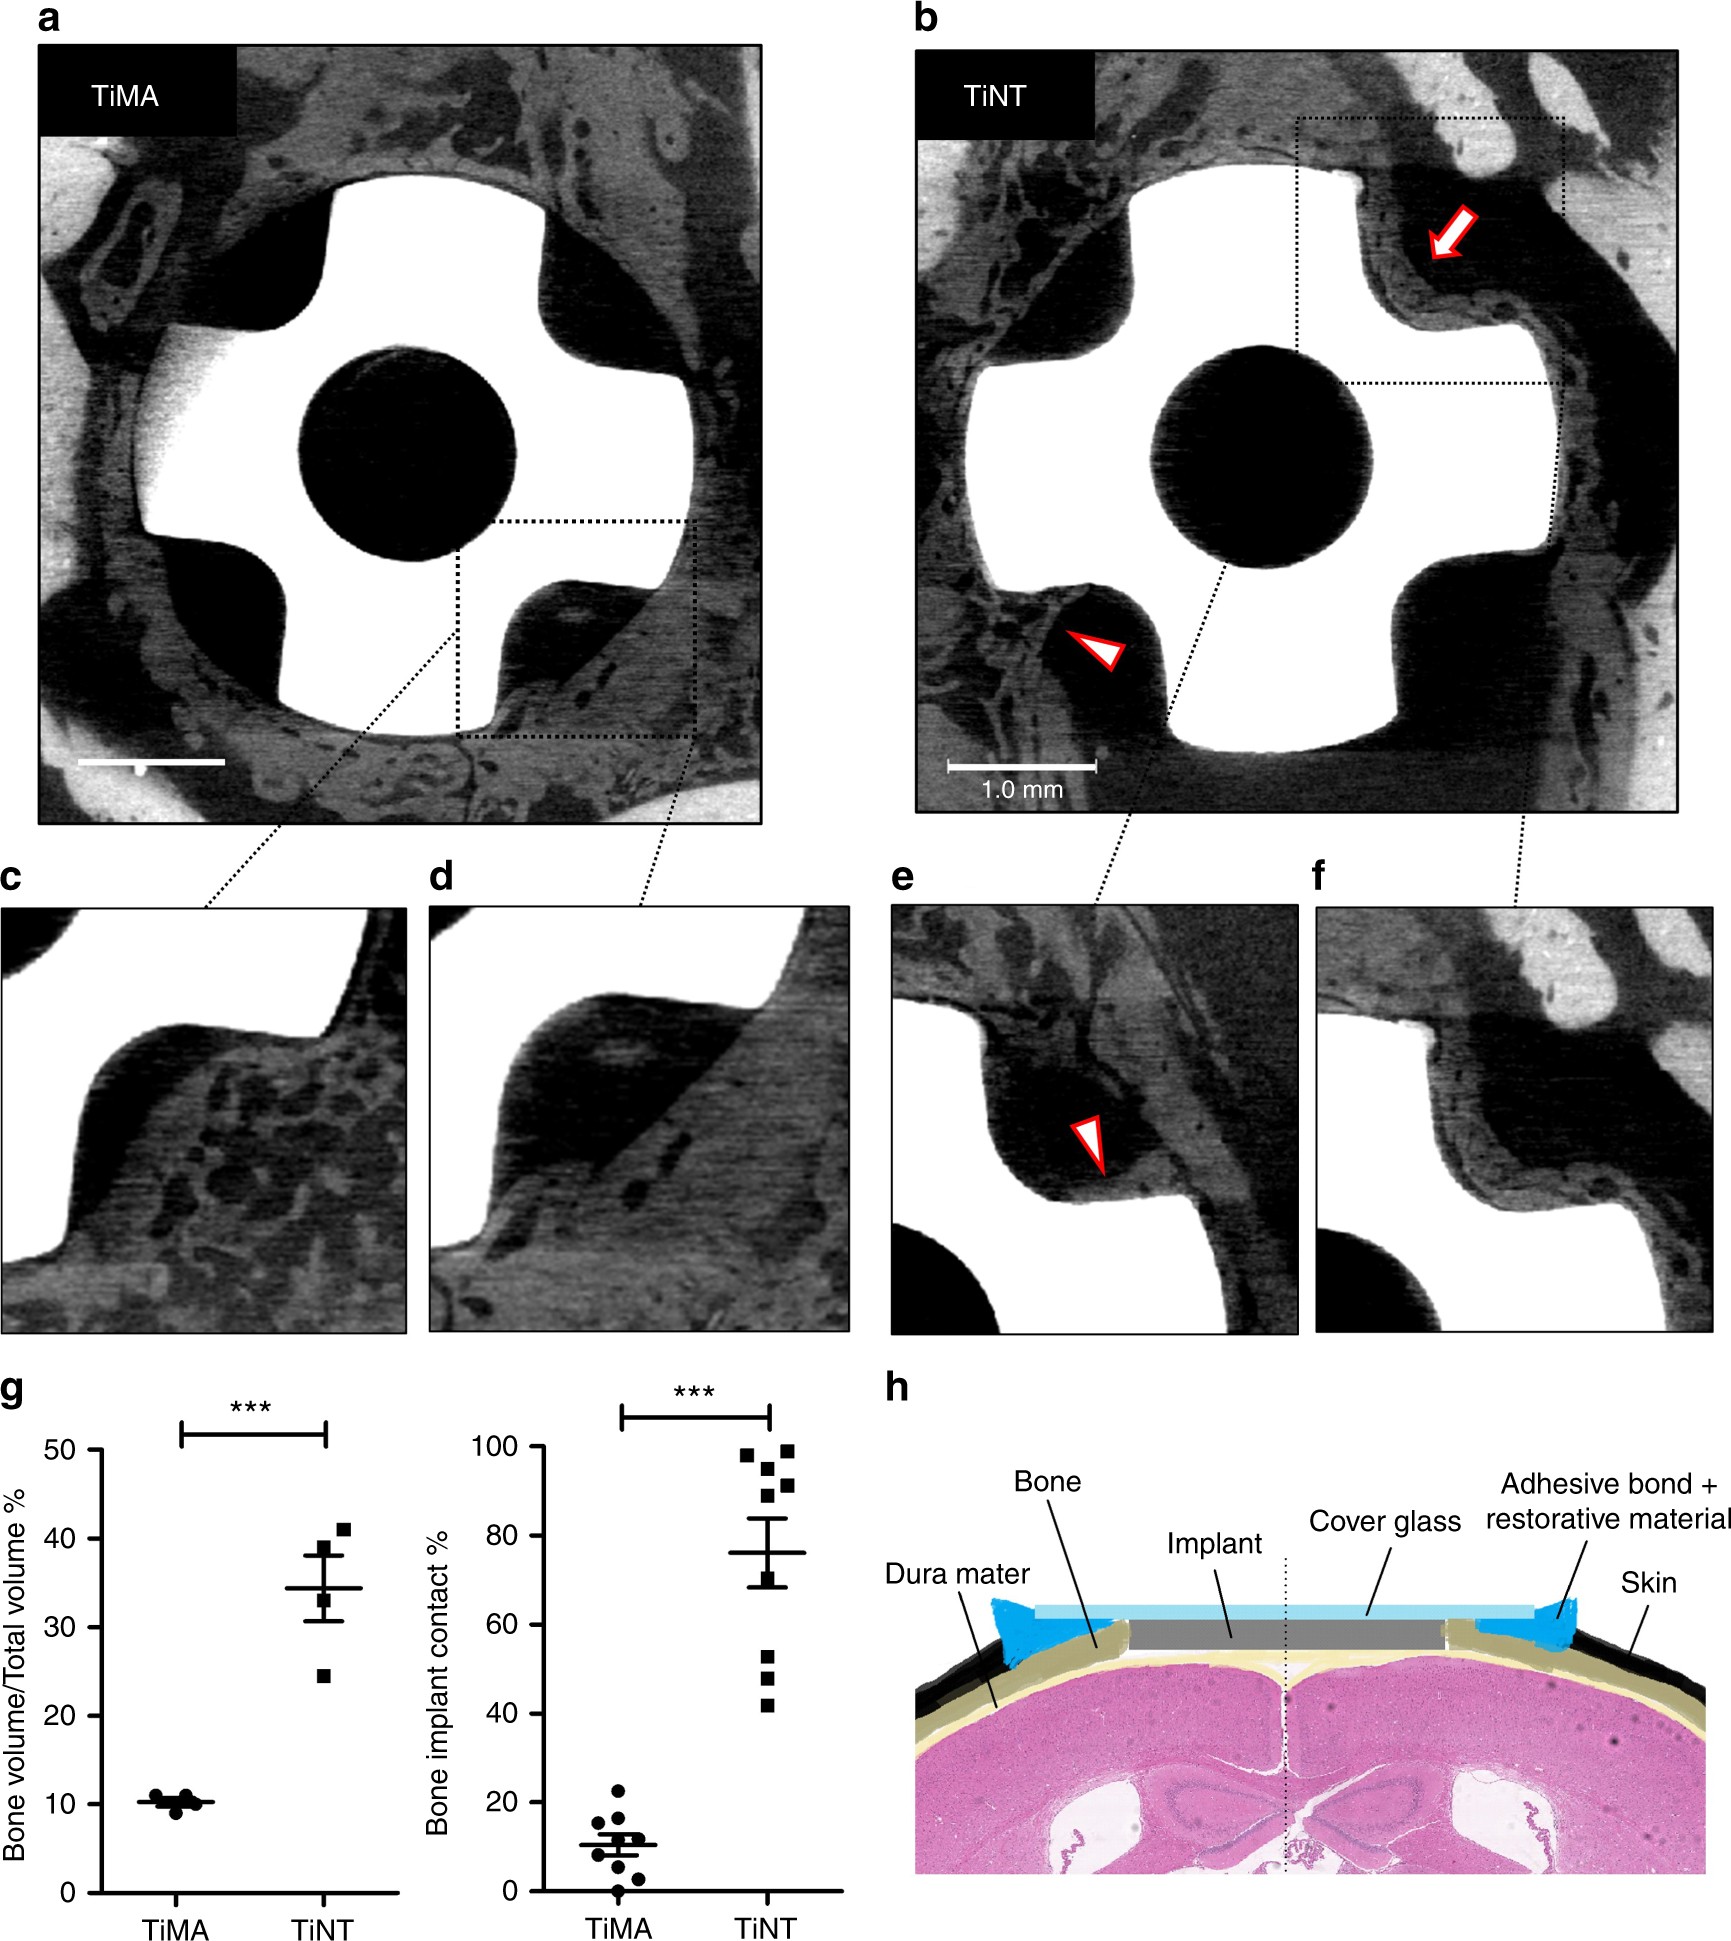

Fig. 4

µCT images showing pattern of osteogenesis in response to implant surface topography. Images of the entire calvarial wound site including the Ti implant in the defect with the a TiMA and b TiNT implants at day 42 post-surgery. Note that the margins of the osteotomy are more easily seen with TiMA implants due to the fact that less bone has grown into the healing volumes. With TiNT implant, in one healing volume the surface of the implant is completely occupied with bone (arrow), and in another bone is growing into the healing volume along the implant surface forming a Baud curve (arrowhead) typical of contact osteogenesis (see text). c–f Magnified images of the scans in a, b but at two different depths in the healing volumes around the c, d TiMA surface and the e, f TiNT surface. Scale bars (a, b): 1 mm. g Quantitative analysis of bone regeneration parameters (Bone Volume/Total Volume and Bone Implant Contact) in TiMA and TiNT groups at day 42 post-surgery. Data is shown as mean ± SEM (n = 4, two-sided Student’s t-test performed to compare groups, ***P < 0.001). h Schematic showing the coronal view of the CIWC